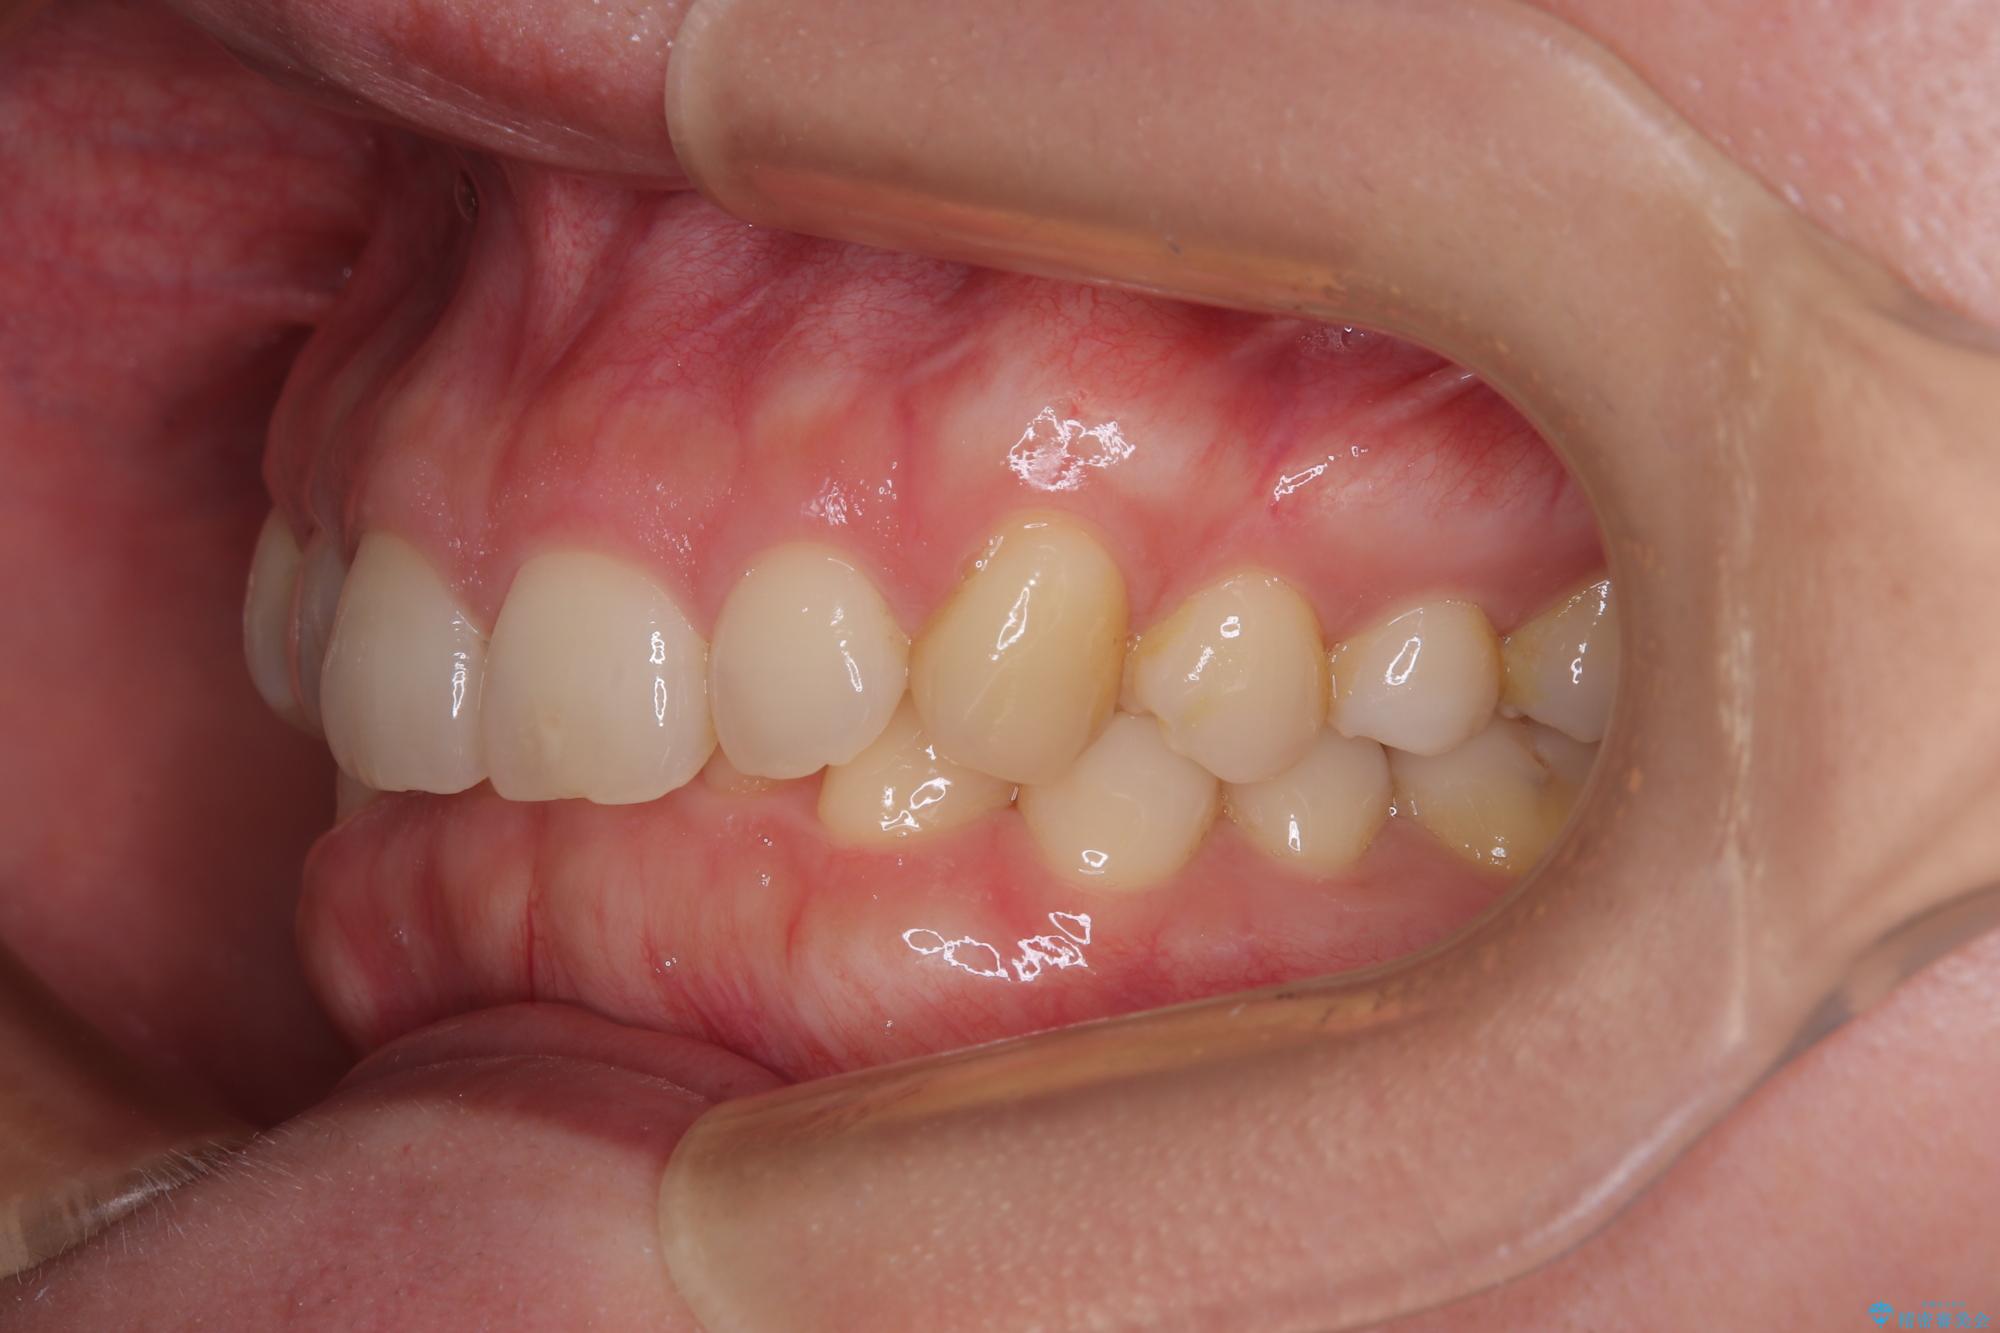

下顎の臼歯が手前に傾斜していることで咬み合わせが深くなってしまい、下顎前歯が見えないほどに上顎前歯が覆い被さっている状態でした。